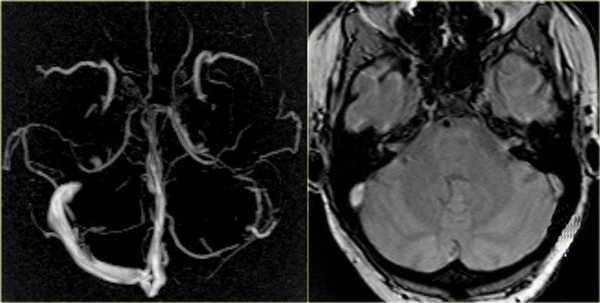

Стандартное лабораторно-инструментальное обследование пациентки (биохимический анализ крови, электрокардиография, рентгенография органов грудной клетки, ультразвуковое исследование сосудов шеи) патологии не выявило. Осмотр офтальмолога: состояние глазного дна — диск бледно-розовый, границы четкие, калибр сосудов не изменен. МР-веносинусография и КТ-ангиография с венозной фазой: крупные вены и синусы не изменены, за исключением умеренного расширения корковых вен среднего и дистального сегмента справа (на уровне верхней анастоматической вены Тролярда) (рис. 2), что может служить признаком формирования коллатерального оттока.

ткани [16]. Идентичность очагов при CLIPPERS с очагами нашей больной позволяют расценивать их как сосудистые. Наличие перифокального отека свидетельствует о вовлечении в процесс мелких вен. Подтверждением сказанного является формирование венозных коллатералей (см. рис. 2), локализация очагов в обоих полушариях головного мозга, симметричность их расположения, клиническая картина и, наконец, сама причина заболевания — тромбофилия.

Тромбоз сигмовидного синуса слева при МР-ангиографии (левое изображение) с отсутствием визуализации венозного русла. На нативном снимке (правая картинка) патология не видна